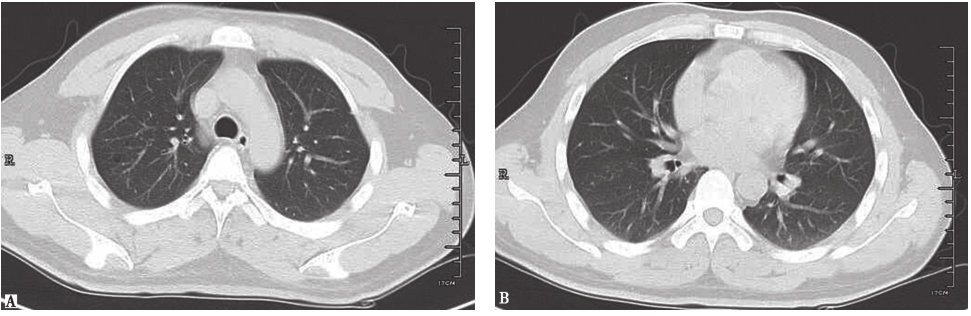

诊断明确后,嘱患者严格戒烟,同时给予糖皮质激素治疗(因合并骨质损害)。患者胸痛症状明显好转,1个月后复查胸部CT示肺部病灶基本吸收(图9)。

图9复查胸部CT表现

PLCH目前尚无标准治疗指南,患者预后也不尽相同。部分病例通过严格戒烟可能自愈,糖皮质激素对于部分有症状的患者有效。联合化疗用于LCH严重累及多系统者。对于急性进展并且出现呼吸衰竭的患者,可以进行肺移植术。本例患者行经皮肺穿刺活检明确诊断后,鉴于患者尚有胸痛症状,ECT提示肋骨代谢活跃,故在督促患者严格戒烟的同时加用糖皮质激素。1个月后复查胸部CT显示病灶基本吸收。